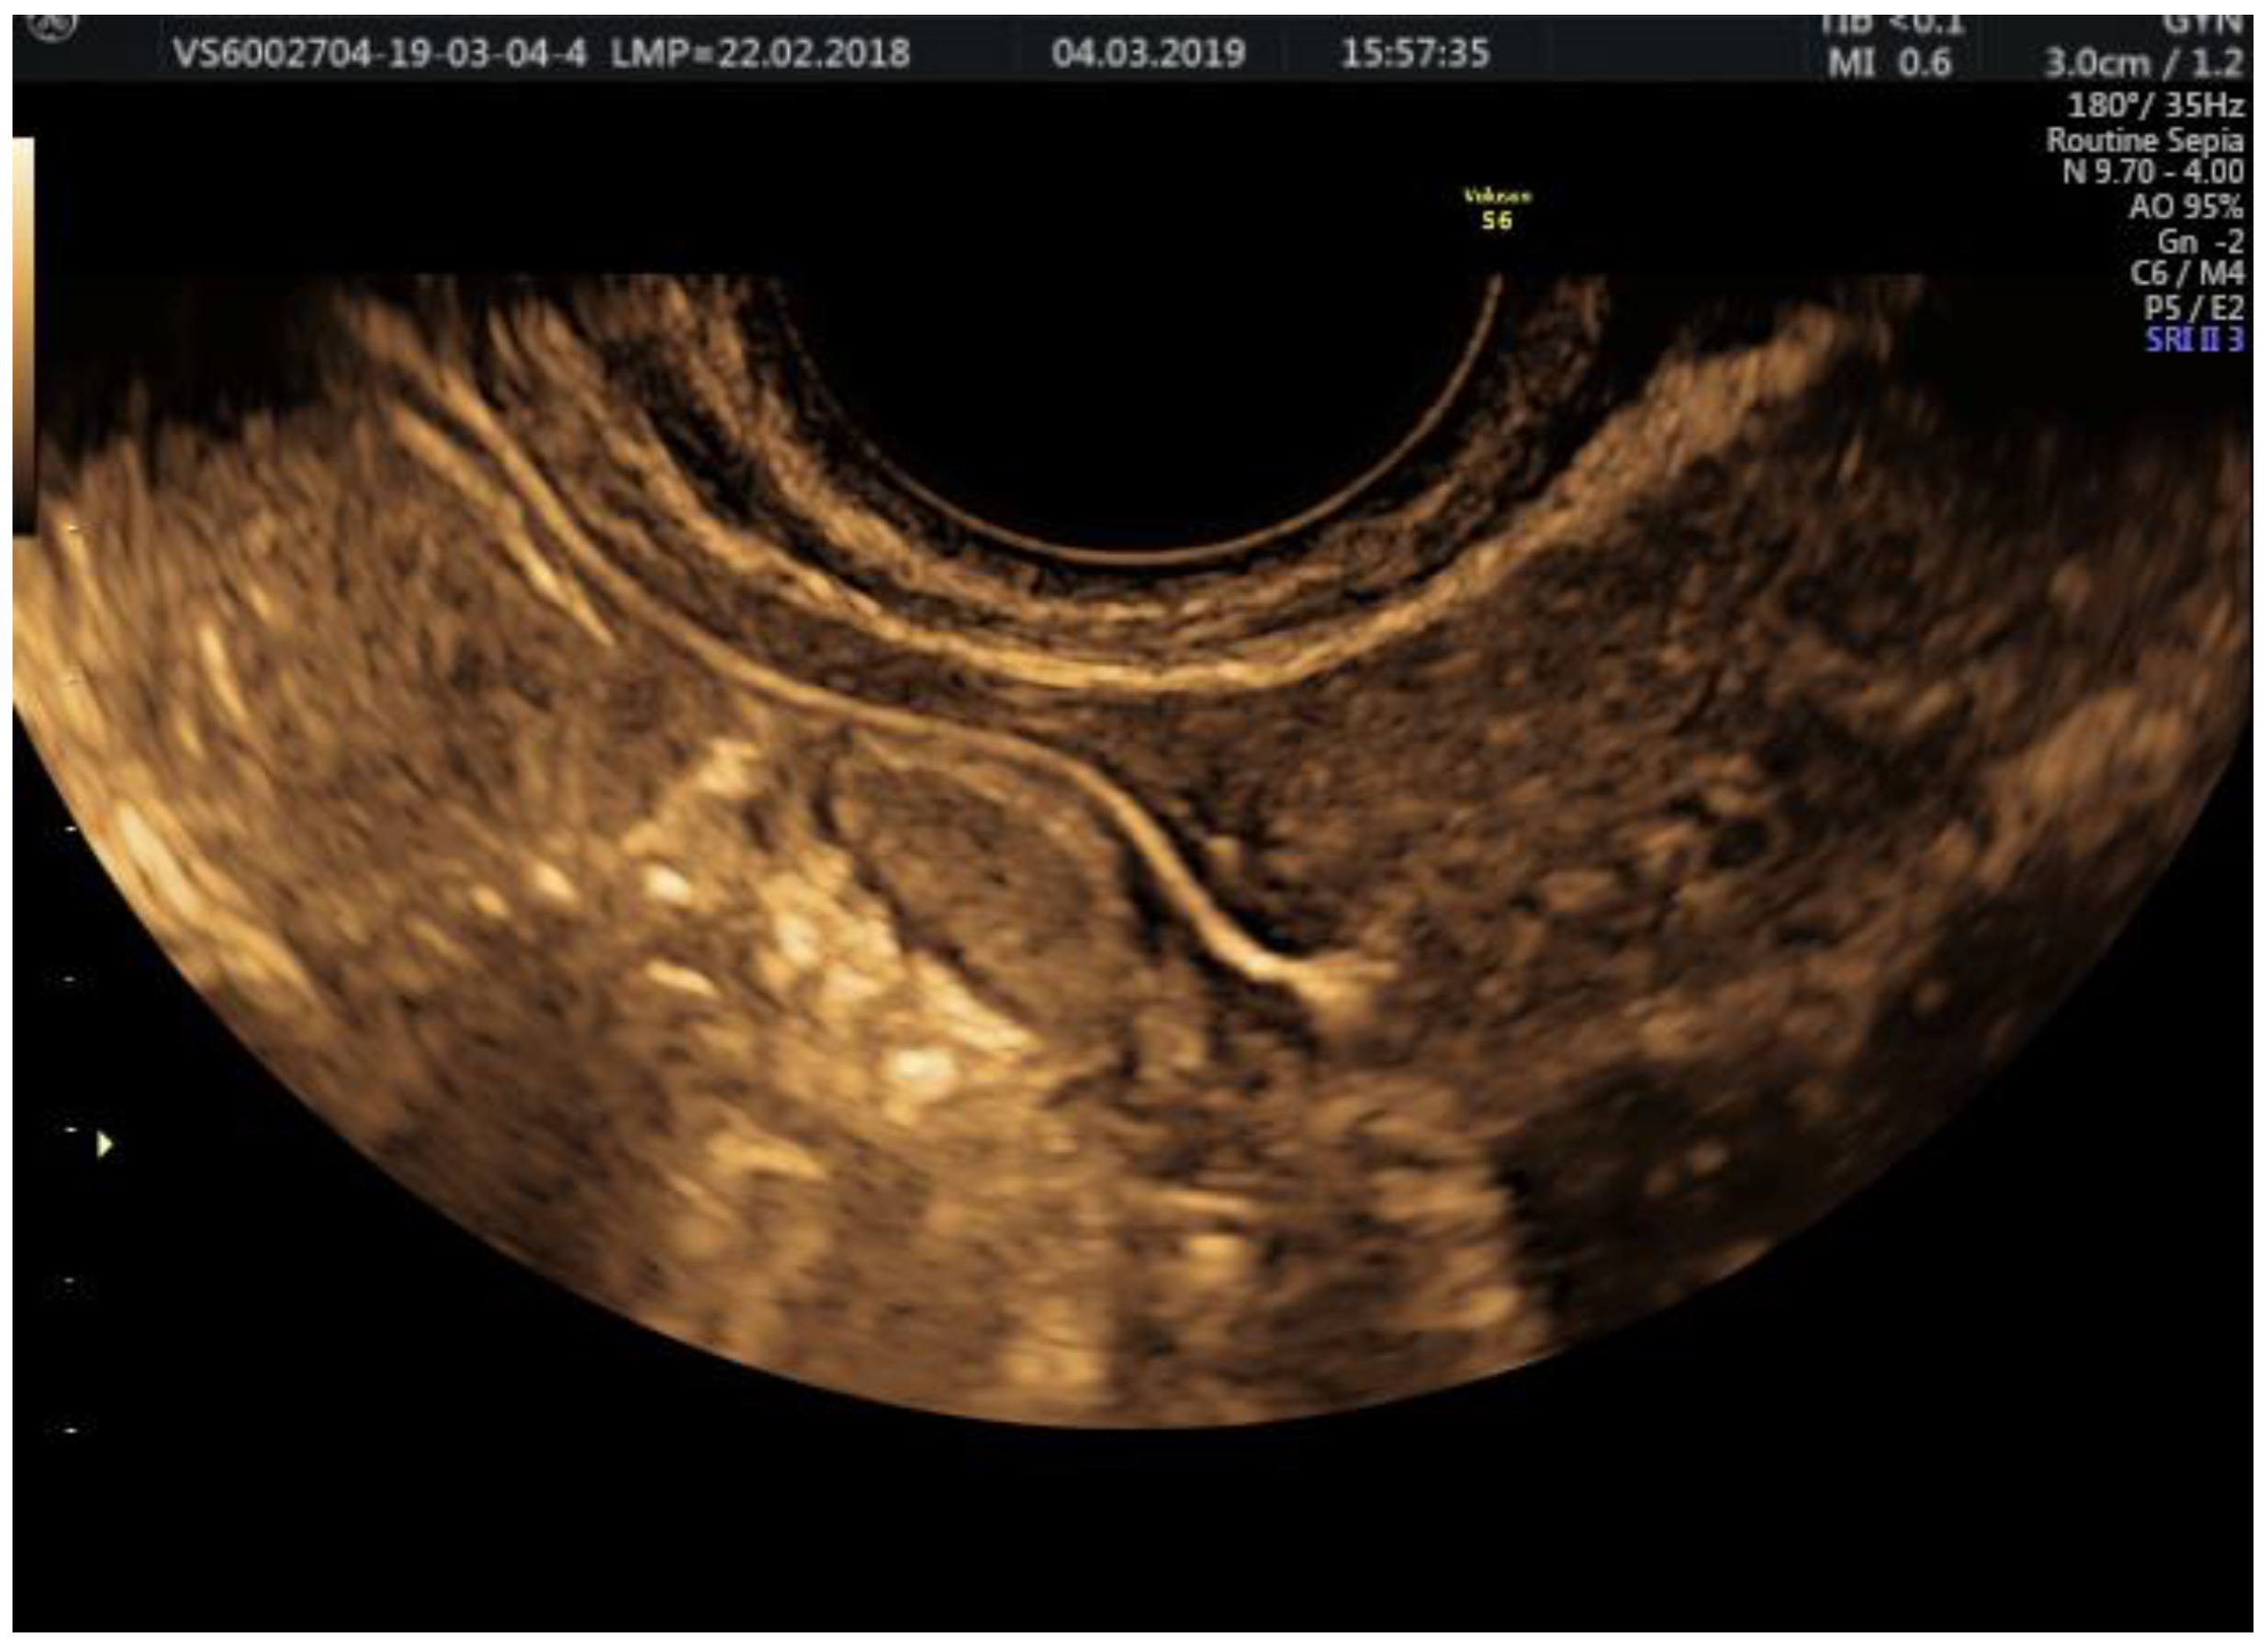

| Tubal patency evaluation requires evaluating the entire substance passage through the tubes | Visualizing the contrast substance progression through the entire tubal pathway, its evacuation near the ovary, and finding the contrast substance at the end of the procedure in the pouch of Douglas or as a fine hyperechoic line near the uterus | Thin line of contrast substance visualized from the interstitial to the infundibular part of the fallopian tube and contrast substance present in the cul-de-sac are signs of tubal patency [31] |

| The use of 2D sepia mode | The functional dynamics of the tubes are optimally evaluated; Using 3D mode on HG-Flow offers spectacular images without acquiring a real informational benefit | 3D-HyFoSy, with or without Doppler techniques, does not bring additional information compared to 2D-HyFoSy when used by a ultrasonographer who has knowledge of the pelvic anatomy [29] |